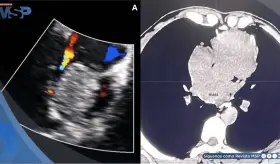

Más de 3,000 saltos al vacío marcaron su juventud. Hoy, desde Puerto Rico, lidera procedimientos complejos transmitidos a nivel global y posiciona a la isla en la vanguardia de la cardiología intervencional.